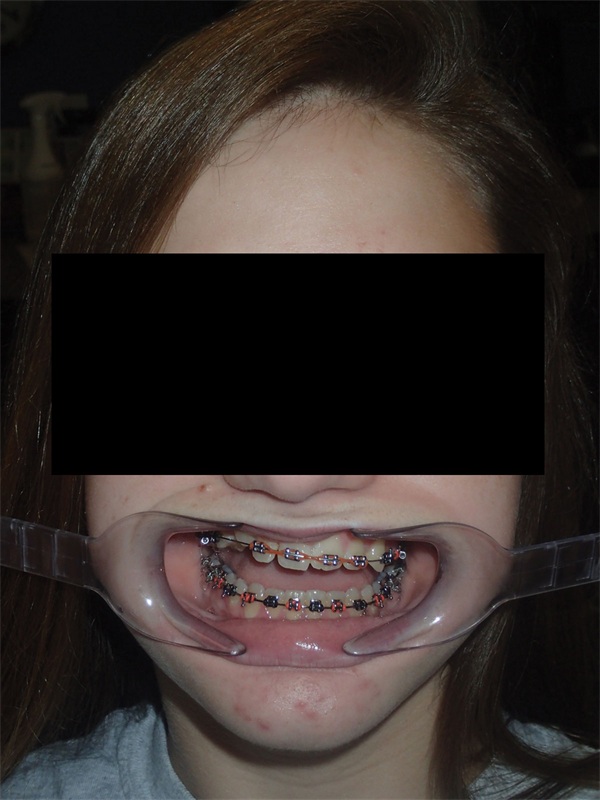

Updated records told a different story. The upper right canine remained fully unerupted, and significant adverse canting of both arches had developed on the right side (Figs. 4–6). Root shortening was visible on the upper right canine, lateral, and central incisors, likely a consequence of prior reluxation attempts to encourage eruption. The upper incisors had also become markedly more proclined over the course of treatment, a known risk when ectopic canines prove resistant to traction. Comparing the pre-treatment and current lateral cephalometric radiographs illustrated just how much incisor angulation had shifted (Figs. 2, 10). Facial photographs suggested some lower-third asymmetry with a right-side deviation, though the lower arch canting appeared to have partially self-corrected after vertical elastics were discontinued (Figs. 7–8).

Fig. 4

Fig. 5

Fig. 6